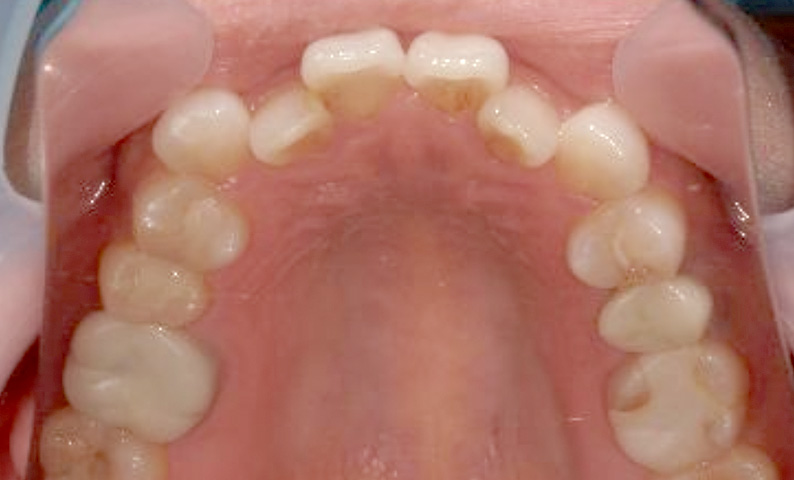

症例_001 上顎だけの部分矯正

治療期間:8ヶ月金額:24万円+税男性すきっ歯上の前歯だけ

| Before | After |